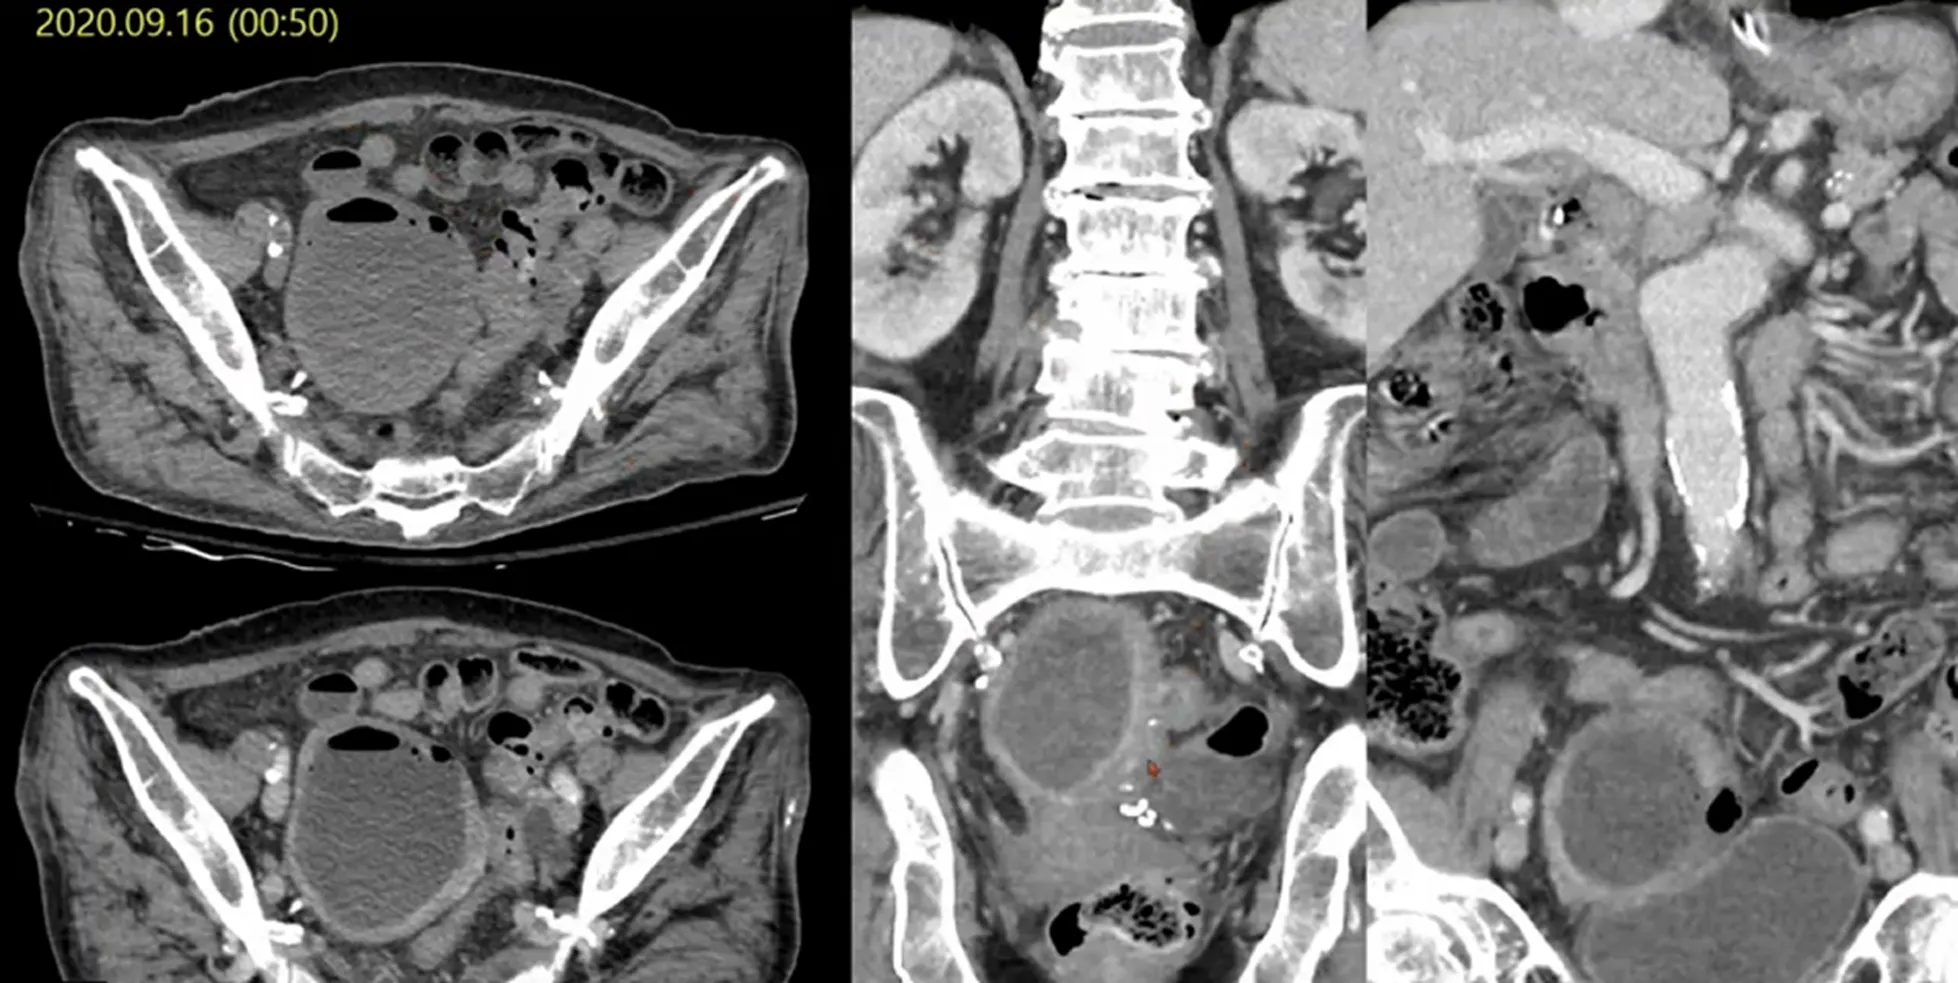

Case 10-2

•

M/43

C/C: Abdominal pain, aggravation

Hx : h/o ureter stone

Lab: within normal limit